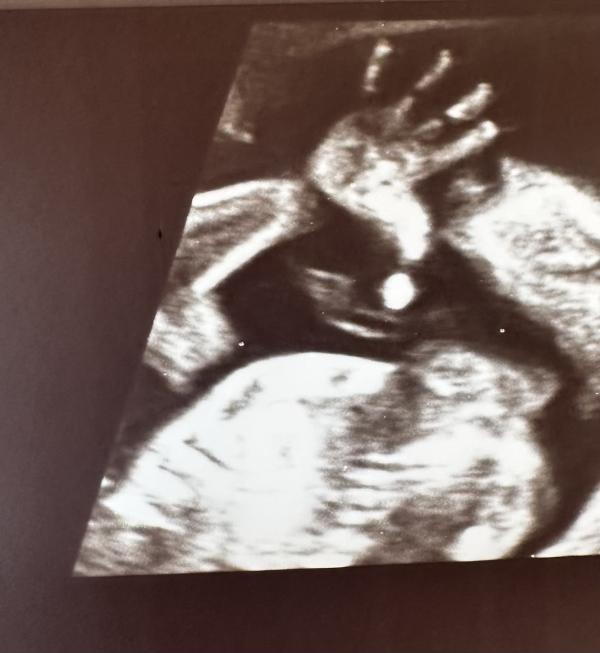

Карапуз был явно в хорошем настроении и показал себя во всей красе ☺️

А еще много махал рукой …

И сосал по очереди пальцы на руках и ногах , наверное не мог определится , где вкуснее 🫢